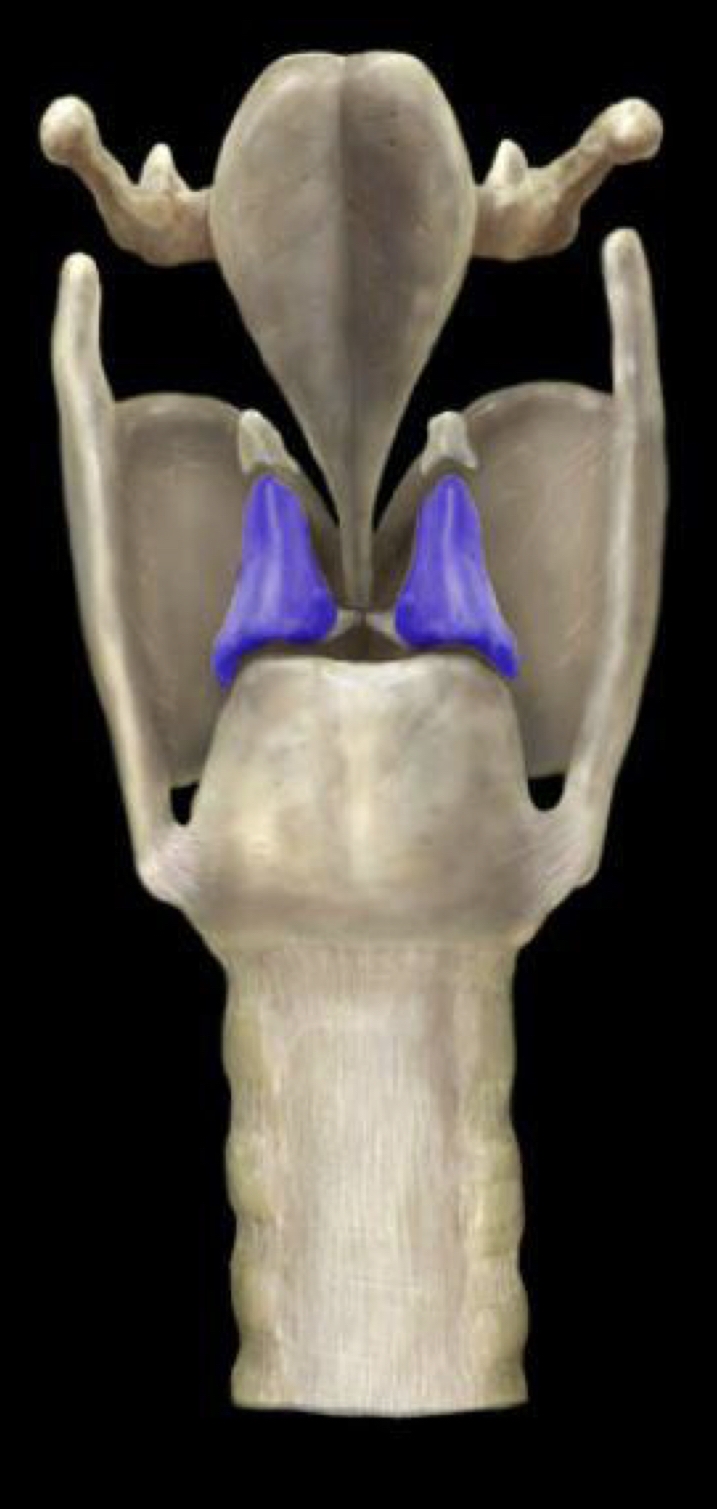

What structure is highlighted in blue?

Arytenoid cartilage

35

New cards

Corniculate cartilage

Cricoid cartilage

Epiglottis

Thyroid cartilage